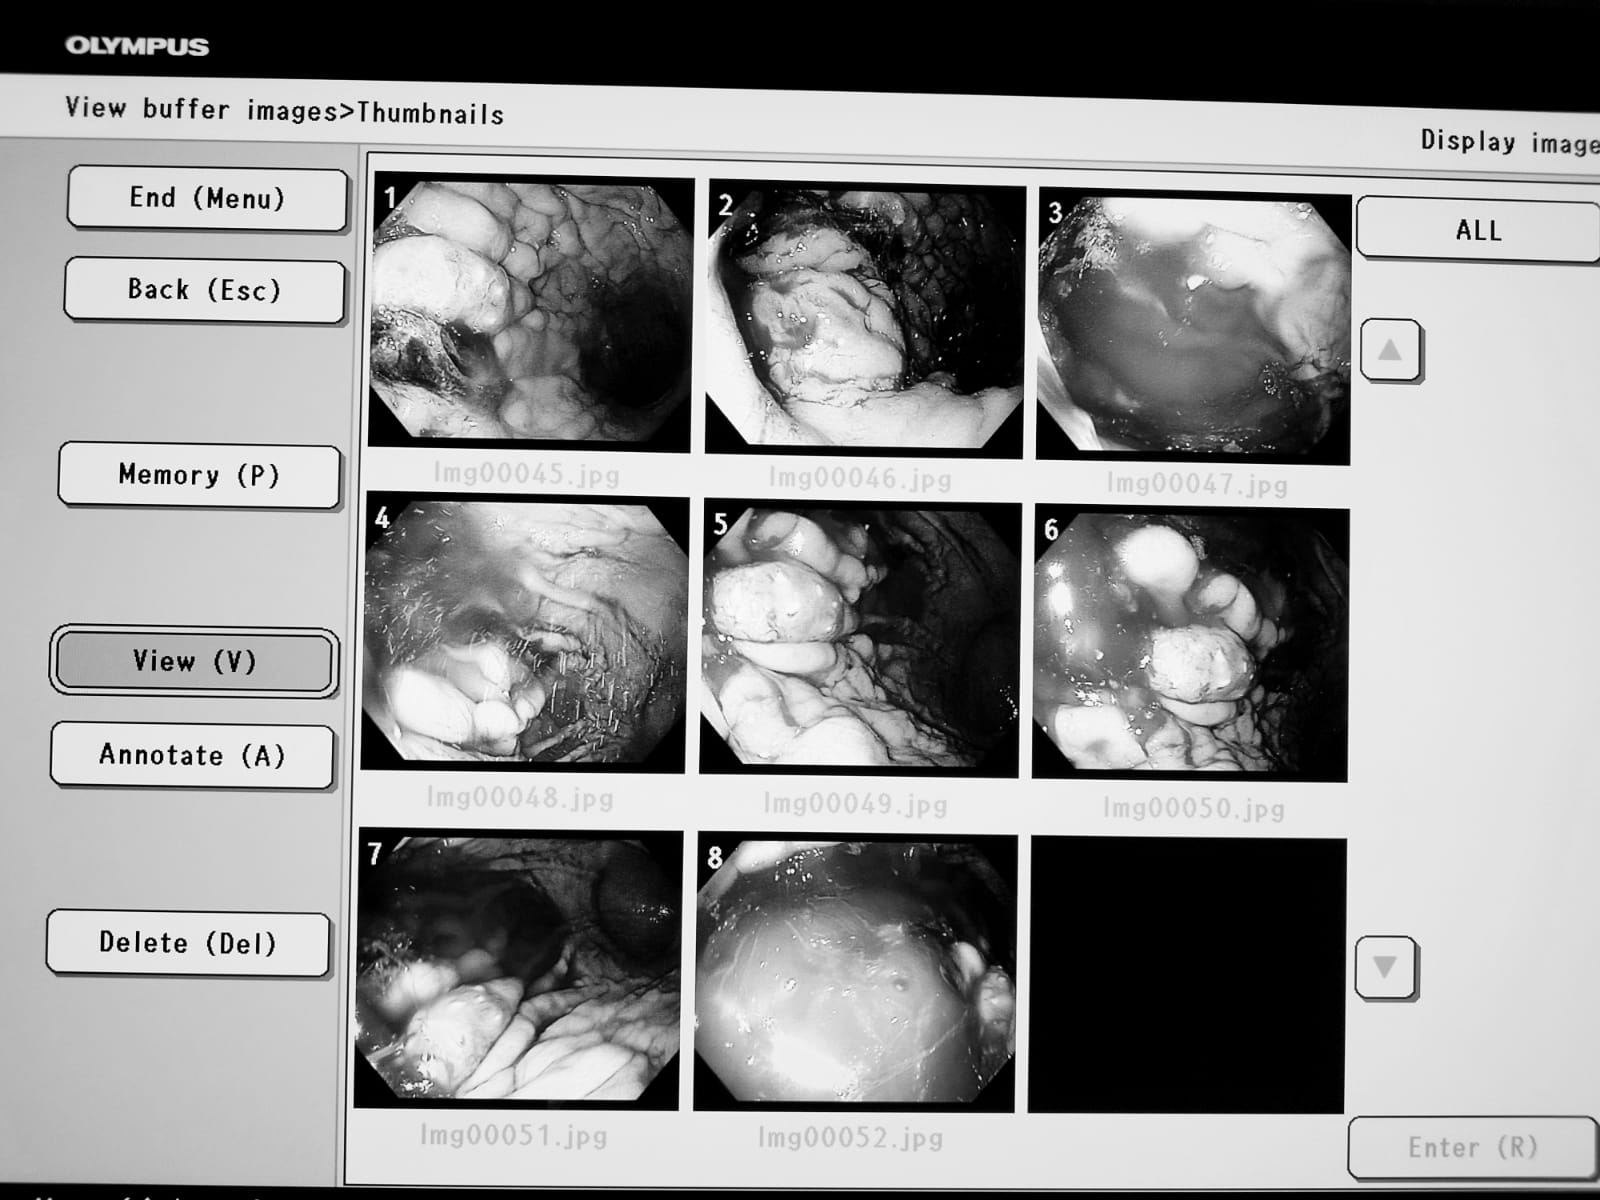

La finalul anului trecut, Consiliul Județean Gorj a finalizat procedura de achiziție iar recent a încheiat etapa de punere în funcțiune și dare în folosință a noului sistem de endoscopie digestivă superioară și inferioară de ultimă generație, care facilitează vizualizarea și examinarea detaliată, fiind compus din:

-Videogastroscop HDTV

-Videocolonoscop HDTV

-Videoprocesor cu posibilitate de configurare a limbii române și înregistrare a datelor pentru 50 de pacienți

-Sursă de lumină

-Tester de imersibilitate

-Aspirator

-Monitor medical LCD

-Troliu endoscopie

Astfel, din data de 20.01.2023 până în momentul de față, cu noul echipament medical au fost efectuate 29 de endoscopii și 15 colonoscopii, conform datelor transmise de reprezentanții SJU Târgu Jiu.

Noul echipament medical permite investigarea endoscopică cu bandă îngustă de culoare, care are rolul de a evidenția capilarele și structurile de pe suprafața mucoasei, ceea ce duce la o mai bună delimitare a leziunilor de la nivelul mucoasei.

„O afecțiune depistată la timp este mai ușor de tratat, iar prognosticul pentru pacient este mult mai bun. Este un aparat ultraperformant, mai ales datorită tehnicii NBI-narrow band imaging. Superioritatea aparatului se datorează tocmai tehnicii NBI, ceea ce îl diferențiază de alte aparate existente. Este creat un contrast sporit între vasele de sânge din mucoasa digestivă și țesuturile adiacente. Această tehnică ajută în depistarea precoce a tumorilor digestive și a altor leziuni inflamatorii din peretele digestiv. Acest fel de aparat există în clinicile și spitalele universitare din țară. De noul sistem endoscopic beneficiază atât pacienții internați în Secția Gastroenterologie, cât și ceilalți pacienți ai Spitalului Județean de Urgență Târgu Jiu, pe internare continuă, sau internare de zi”, a menționat dr. Roxana Gheorghițoiu, medic specialist gastroenterologie din cadrul Spitalului Județean de Urgență Târgu-Jiu.